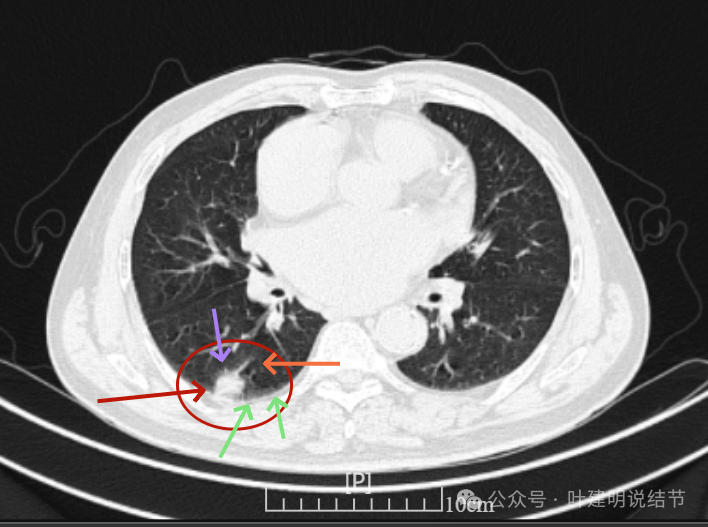

再看2024年6月时的影像:

右下新增病灶,混合密度,整体轮廓较清,瘤肺边界欠清。

有小血管进入,边缘毛糙。

局部有毛刺,但不够锐利;病灶感觉有一层晕似的,邻近胸膜下也有淡磨玻璃影。

实性密度为主,周围少许很淡的磨玻璃影。

边缘不平有毛刺,但不锐利;贴着胸膜但无明显牵拉。局部表面有浅分叶似的,但总体膨胀感不够。

病灶表面不光滑,边上有晕,邻近有淡磨,贴着胸膜无牵拉。

病灶边缘欠清晰,瘤肺边界稍模糊。较宽的基底贴着胸膜。

病灶有血管进入,有浅分叶,实性为主,邻近胸膜有片状淡磨玻璃影,近胸膜无牵拉。但有一定膨胀性。

病灶实性,与血管关系较为密切。

血管走向病灶,但似乎没有被病灶影响,有向内侧的分支甚至没有哪怕一点凹向病灶侧。整体显得偏模糊。

边缘区域杂乱,边糊。